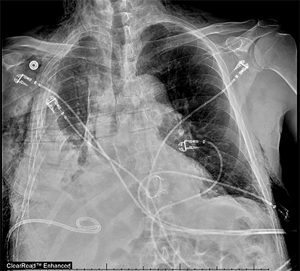

Custy went to the hospital’s Surgical/Trauma Intensive Care Unit, where staff helped to manage his breathing and pain, which was considerable. For a week, Peltz and his team consulted with Custy and his family. They decided to wait in hopes of the ribs beginning to heal together, but his punctured lung slowly collapsed, cutting its capacity by 30 percent. He was at risk for pneumonia and “permanent, severe pulmonary disability,” Peltz said.

On the last day of June, Peltz and cardiothoracic surgeon Robert Meguid, MD, MPH, decided Custy couldn’t afford to let nature take its healing course. They turned to hardware to repair the fractures: horseshoe-shaped titanium devices fitted over the front and back of each rib and secured with screws. These “rib plates” also helped to stabilize Custy’s chest wall, Meguid said. He and Peltz also drained blood out of the pleural cavity, allowing the right lung to expand. In addition, they found that a shard of one of the fractured ribs had sliced his diaphragm, exposing a portion of his liver. They repaired that laceration during the procedure.